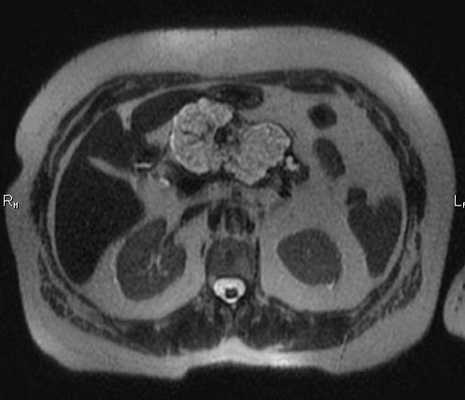

МРТ брюшной полости в корональной плоскости. Очаговые кистозные образования печени паразитарной природы, округлой формы, с четкими и неровными контурами.

МРТ брюшной полости в аксиальной плоскости. Структура железы неоднородная за счет наличия в области тела кистозных образований (серозная цистаденома), сливающихся между собой (разделенных тонкими перегородками), с достаточно четким и неровным наружным контуром. Содержимое образований характеризуется однородным гиперинтенсивным сигналом на Т2-ВИ.